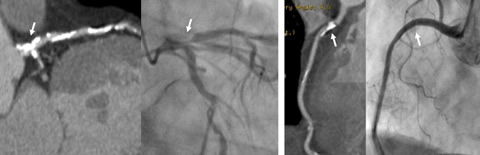

心臓CTは、冠動脈造影に匹敵する詳細な画像が得られ、プラークによる冠動脈の狭窄や閉塞の診断ができます。さらに、急性冠症候群の原因となる冠動脈の壁性状の評価も可能で治療方針の決定に役立っています。

- 冠動脈の石灰化が強い場合、心臓CTで狭窄の有無の判定は困難である(下図参照)。